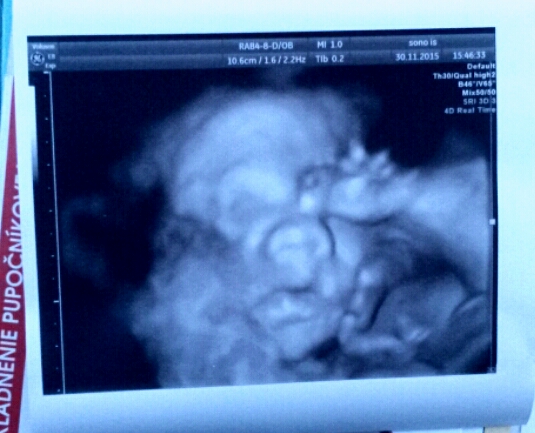

Termín pôrodu marec 2016